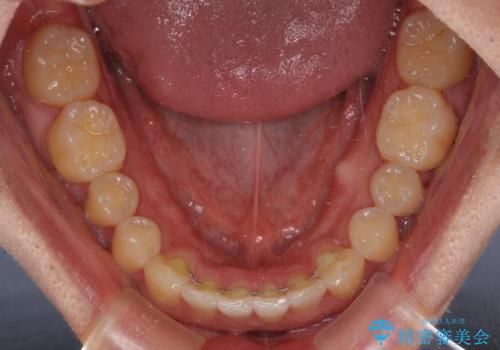

- 前歯のデコボコを気にして来院された患者様です。

主に下顎歯列全体の後方移動とIPR(歯と歯の間を削る)によってデコボコが解消するように設計し、インビザラインにより治療を行うこととしました。

インビザライン矯正特有の、治療後半で前歯のみが強く接触する症状が発現し、咬み合わせ改善に期間を要することとなりました。